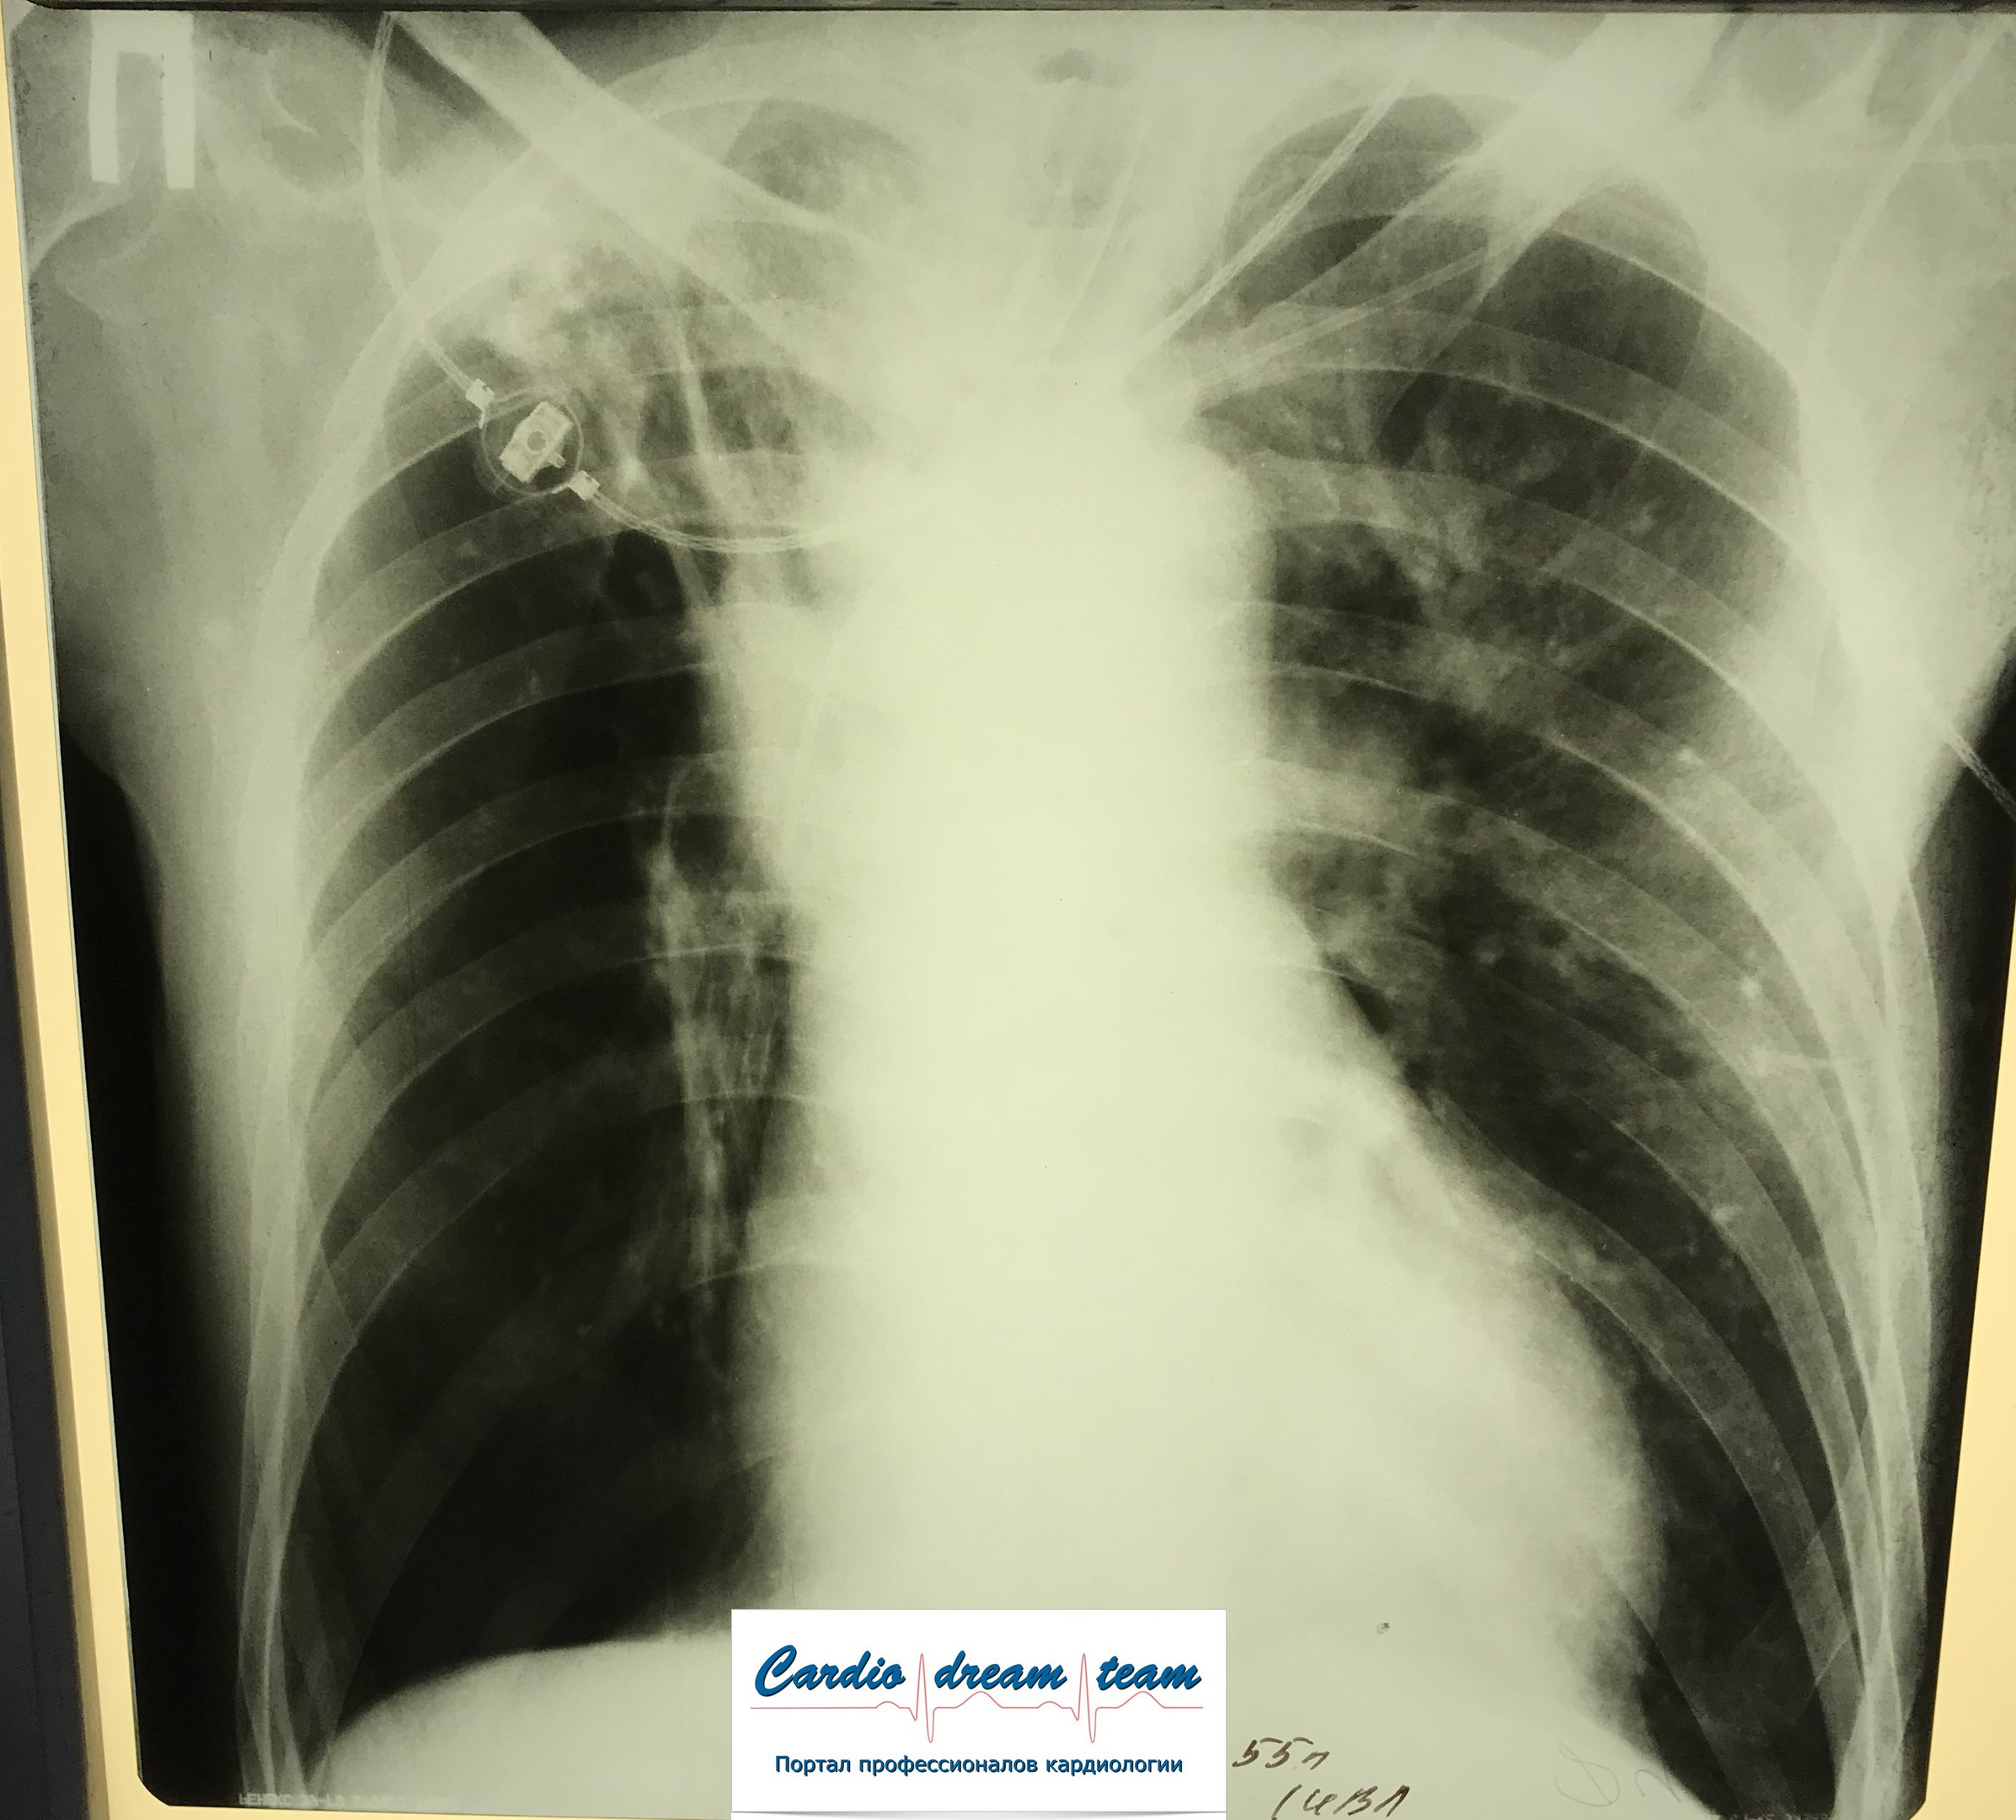

диссеминированный туберкулез легких

Изображение

Обсуждалось здесь viewtopic.php?f=24&t=845